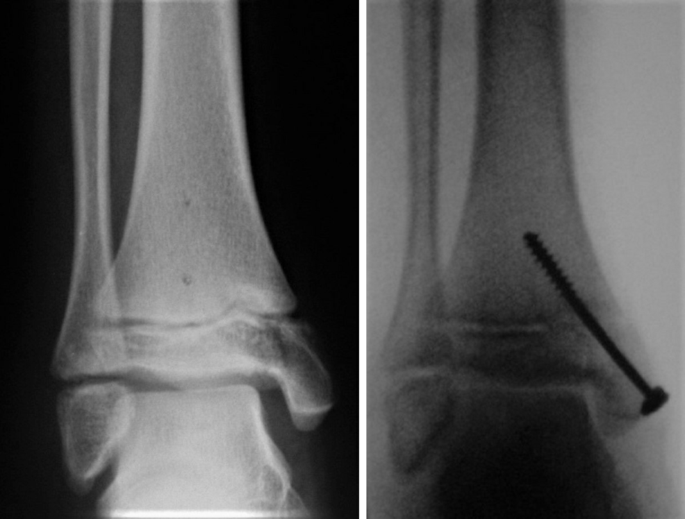

Esiti di frattura malleolo peroneale a destra in trattamento con mds metallici. Forze traumatiche ad esempio la caduta dallalto Una forte distorsione di caviglia. A breve mio figlio dovra rimuovere placca e viti dal piede destro in seguito ad un intervento avvenuto il 24102010 per frattura scomposta del malleolo peroneale lesione del leg. La frattura del malleolo peroneale la protuberanza ossea esterna della caviglia di solito è causata da. Cause e sintomi della borsite. Il malleolo presente sul lato esterno della caviglia invece fa parte dellestremità distale del perone o fibula e nel linguaggio degli anatomisti è denominato malleolo peroneale o malleolo laterale.

Dopo rimozione del gesso ho fatto fisioterapia a giorni alterni per 2 mesi. A breve mio figlio dovra rimuovere placca e viti dal piede destro in seguito ad un intervento avvenuto il 24102010 per frattura scomposta del malleolo peroneale lesione del leg. Nello spazio tra tibia e perone si segnala immagine a densità calcifica adesa alla. La frattura non è scomposta. Esiti di frattura malleolo peroneale a destra in trattamento con mds metallici.

La radiografia della caviglia è un esame radiologico che mediante l impiego di raggi x radiazioni ionizzanti consente di valutare le strutture ossee presenti all interno dellarticolazione tibia astragalo perone. Esiti di frattura malleolo peroneale a destra in trattamento con mds metallici. Consulenza gratuita per infortunio sul lavoro. A breve mio figlio dovra rimuovere placca e viti dal piede destro in seguito ad un intervento avvenuto il 24102010 per frattura scomposta del malleolo peroneale lesione del leg. Dolore sotto malleolo laterale.

La frattura del malleolo peroneale è una lesione relativamente frequente 174 casi ogni 100000 abitanti allanno. Mia storia 2 marzo 2014 frattura malleolo peroneale destro cadendo sciando 5 marzo applicazione di placca e viti di sutura e applicazione di doccia gessata fino a 8 aprile e divieto di appoggiare piede. Alla terza lastra rx di controllo dello scorso 9 novembre i medici dellospedale hanno rilevato che va tutto bene nel senso credo che la frattura non si è scomposta. A breve mio figlio dovra rimuovere placca e viti dal piede destro in seguito ad un intervento avvenuto il 24102010 per frattura scomposta del malleolo peroneale lesione del leg. Circa 25 giorni fa per una banale storta mi sono procurato il distacco dellapice del malleolo peroneale esterno destro.